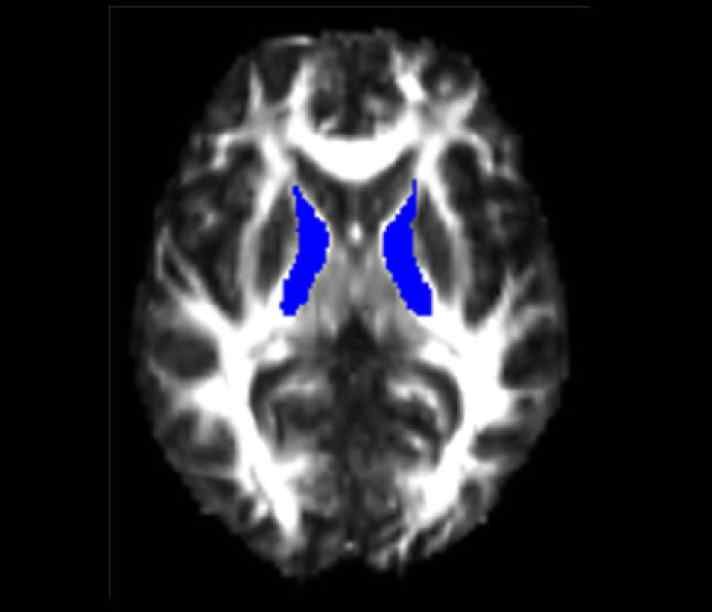

Magnetic Resonance Imaging (MRI)

The Siemens 3T Verio MRI scanner comprises a 70cm diameter open-bore, short-axis magnet. It has been equipped with a comprehensive range of transmit/receive coils suitable for many body regions and applications. The relatively large bore (compared to most MRI systems) ensures a higher degree of subject comfort and compliance.